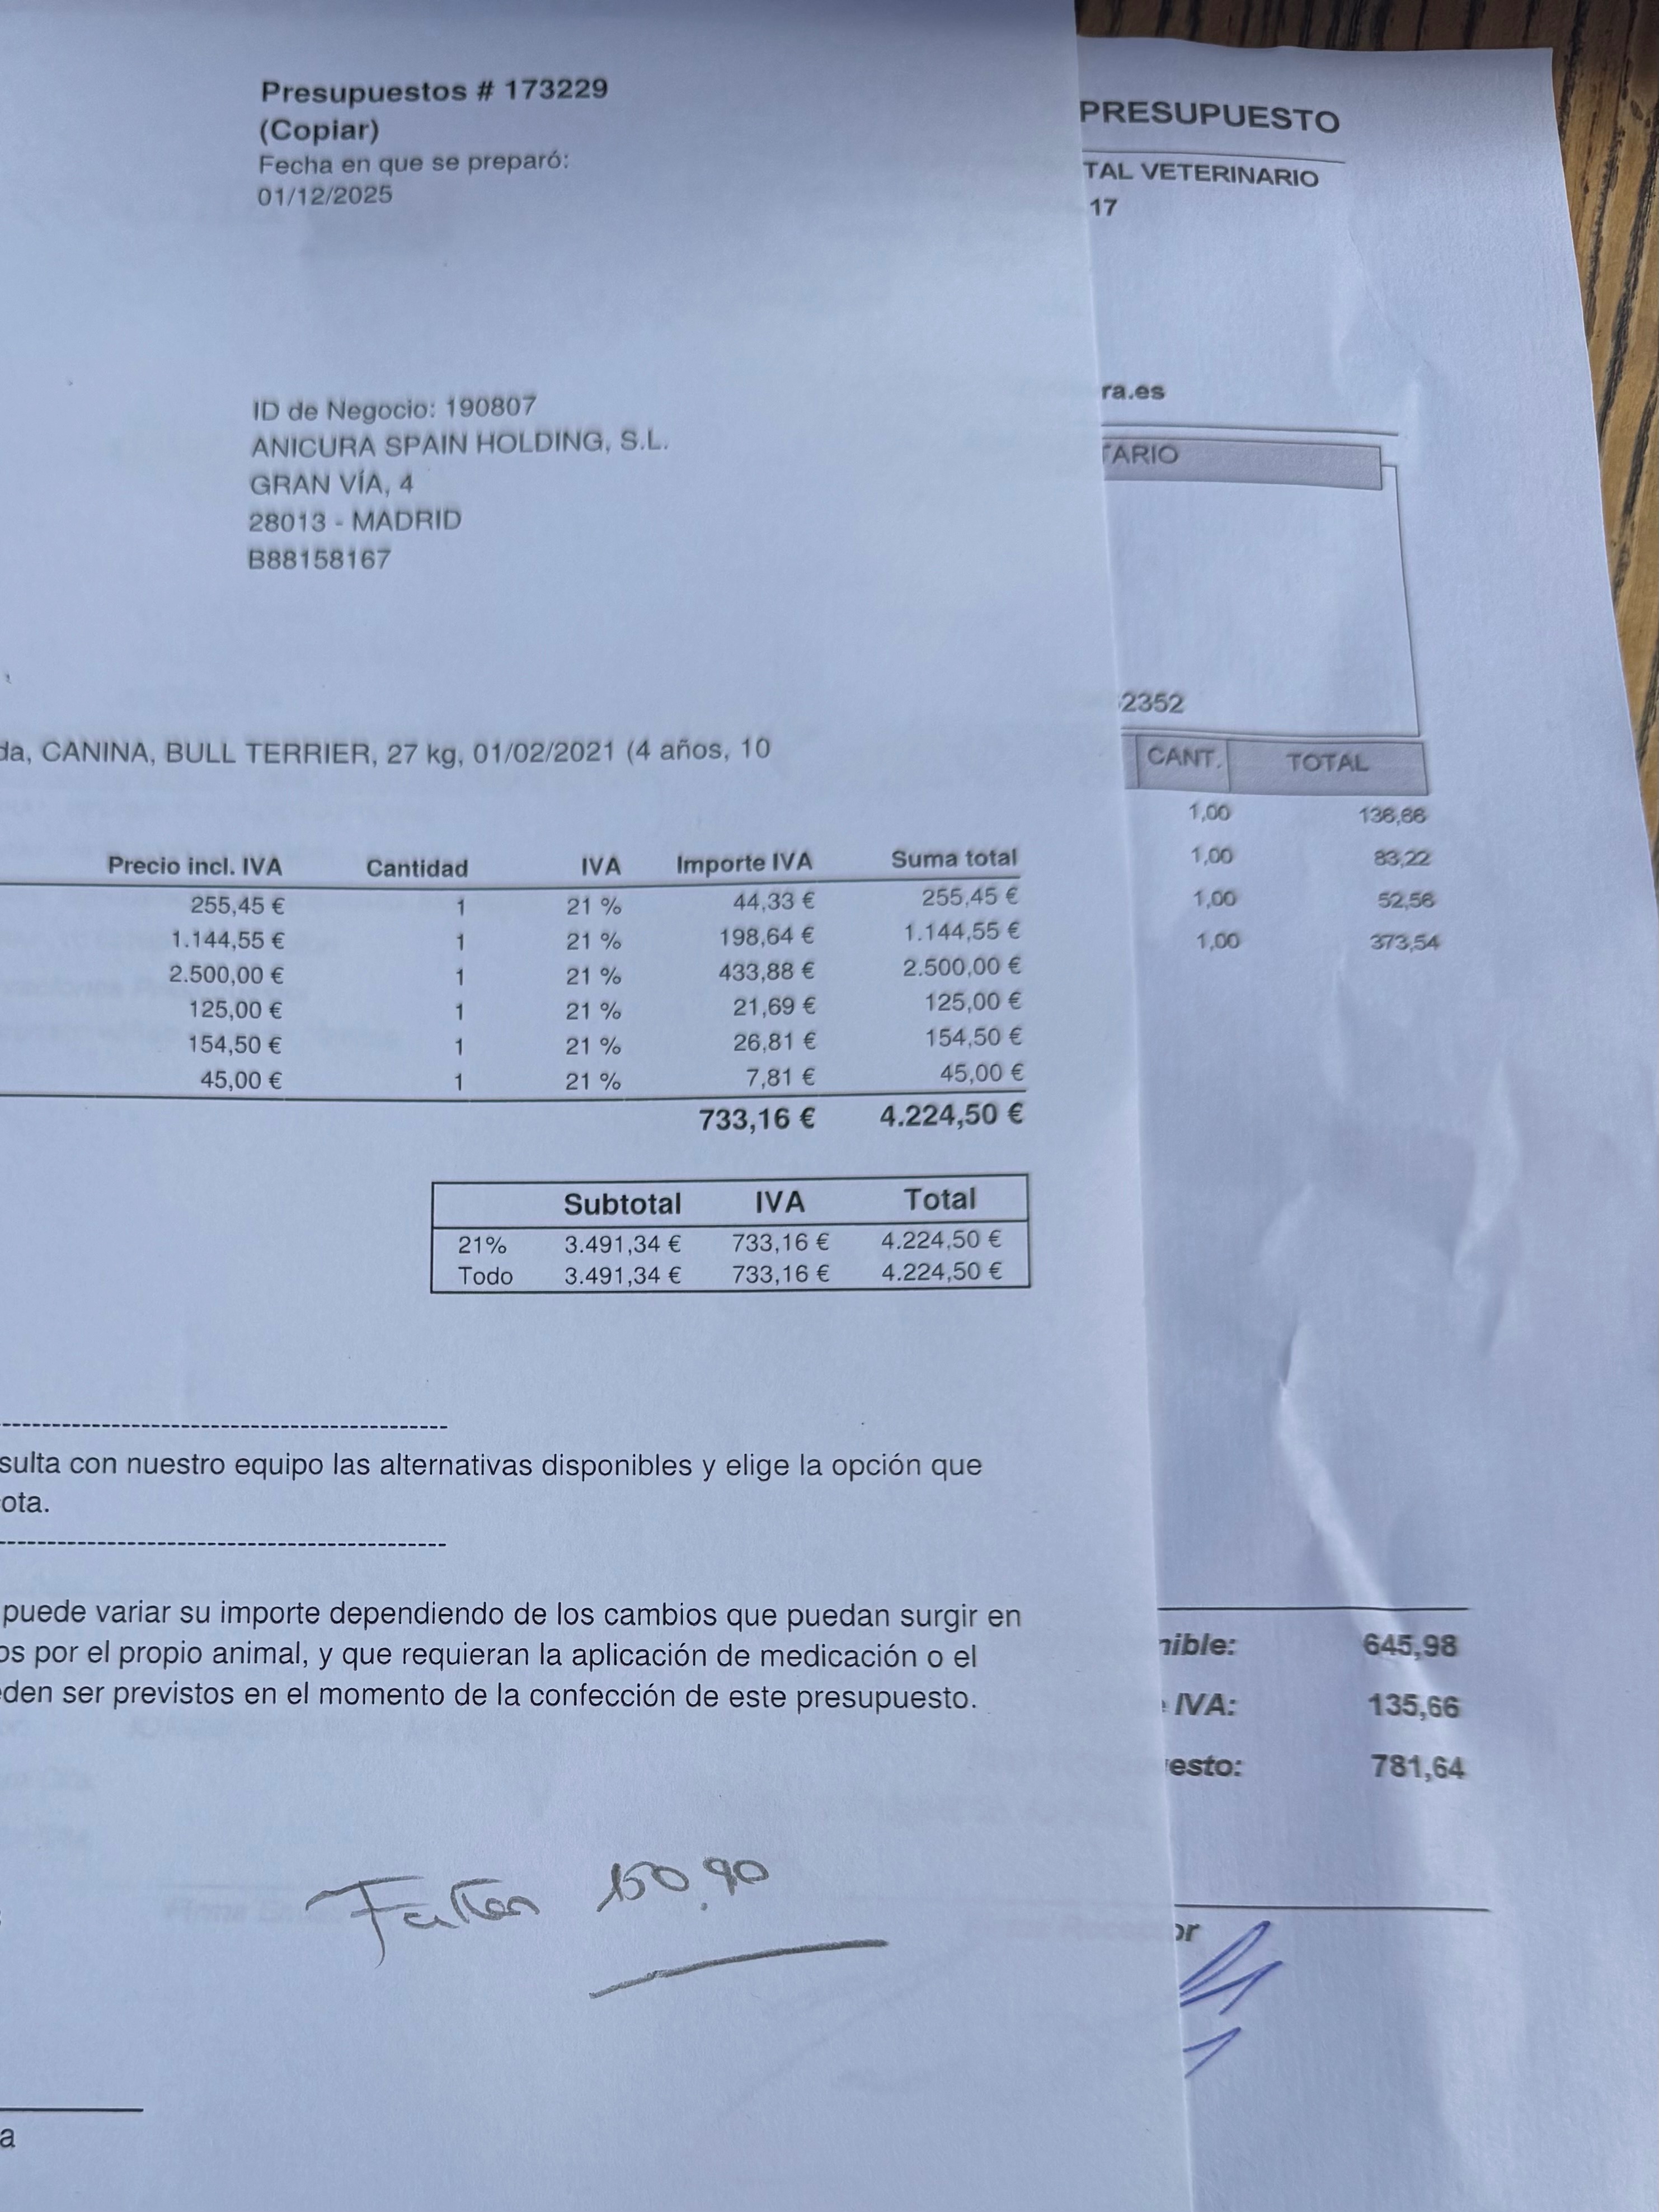

I had a car accident about 24 hours ago and I displaced a vertebrae and broke a femur. I’m in great hands right now and already had the spine surgery which went well. I need your help to cover the expenses and the rehabilitation.

I’ve already gotten through the spine surgery which was a success. I’m now waiting to operate on my femur at the beginning of the week.